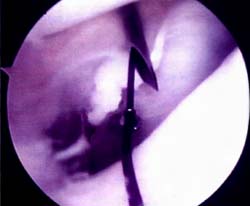

Mediante abordajes laterales superior e inferior se realiza la liberacion con elctrobisturi en forma intrasinovial y a una distancia del borde externo rotuliano de 3 a 5 mm. La completa apertura del retinkulo es la clave del exito en la liberacion. Es de importancia cauterizar las ramas de la arteria geniculada externa con el objeto de evitar hemorragias, post-operatoria. La liberacion se considera completa cuando puede inclinarse la patela a 45° y se visualiza artroscopicamente una apertura completa del retinaculo. (Foto 3)

Foto 1: Vista artroscopica de la Monica de retensa interno.

Foto 2: Vista artroscopica del Cruentado capsulo-sinovia interno.

Foto 3: Vista artroscopica de la Liberacion del retinecu. lateral.